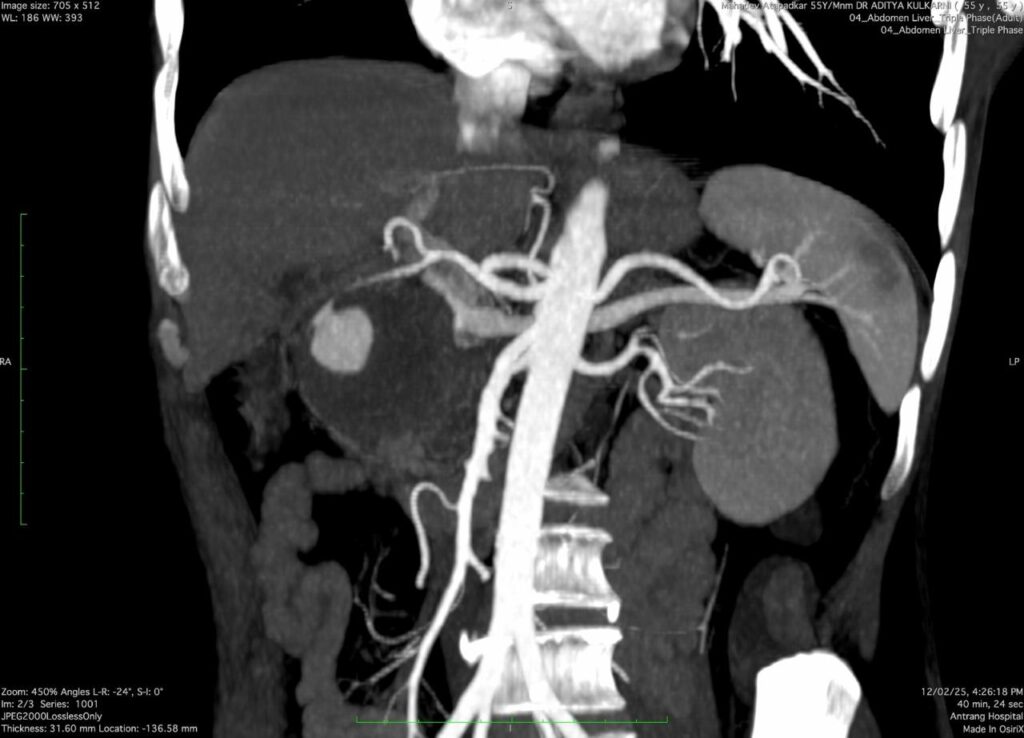

A 53 years- old male presented with a history of repeated GI bleeding for 20days. He had undergone UGI scopy and colonoscopy twice elsewhere with no obvious source of bleed. He was referred to us for further management Initial investigations revealed low haemoglobin levels (3.4), necessitating multiple blood transfusions. CECT abdomen done revealed 4.2×3.4cm pseudo aneurysm arising from Gastro duodenal artery branch within pseudocyst. There was bleeding within pseudocyst. Endoscopic ultrasound (EUS) guided coil +glue was performed to manage the pseudo aneurysm. Post procedure imaging showed Complete Occlusion of the pseudo aneurysm, and the patient was stabilized with supportive care, including IV fluids, antibiotics, and proton pump inhibitors (PPI)

Pseudo aneurysms in chronic pancreatitis are rare but can be fatal due to spontaneous rupture. The primary arteries involved are the splenic, gastroduodenal arteries. The diagnostic approach includes contrast- enhanced computed tomography (CECT), magnetic resonance angiography (MAR), and catheter angiography. Management options include endovascular interventions such as coil embolization or glue injection, surgical resection, or a combination of both as per the local expertise.